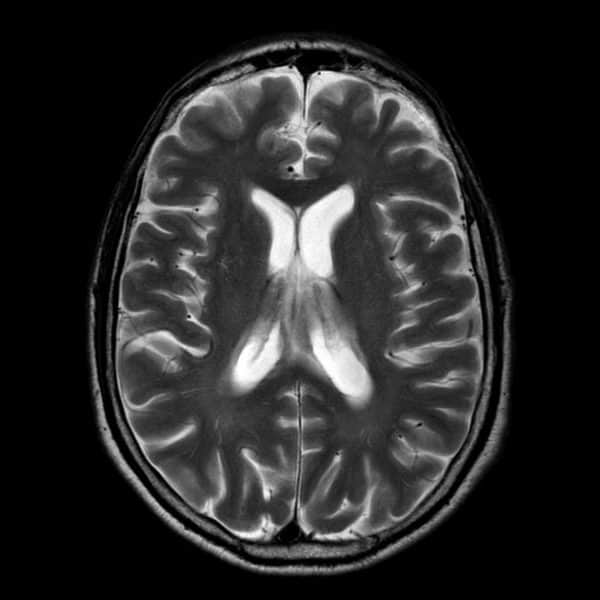

Lymphoma

» Thông tin: Nữam giới – 60 tuổi.

» Lâm sàng: Rối loạn tri giác.